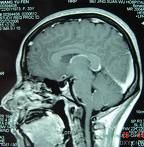

空蝶鞍綜合徵(emptysellasyndrome)系因鞍隔缺損或垂體萎縮,蛛網膜下腔在腦脊液壓力衝擊下突入鞍內,致蝶鞍擴大,垂體受壓而產生的一系列臨床...

蝶骨在顱中窩中間部分高起,形如馬鞍的骨結構。蝶鞍中央凹陷叫垂體窩,容納腦垂體。正常情況下,蝶鞍與腦垂體之間緊密相貼,幾乎沒有空隙。當各種病理因素導致蝶鞍...